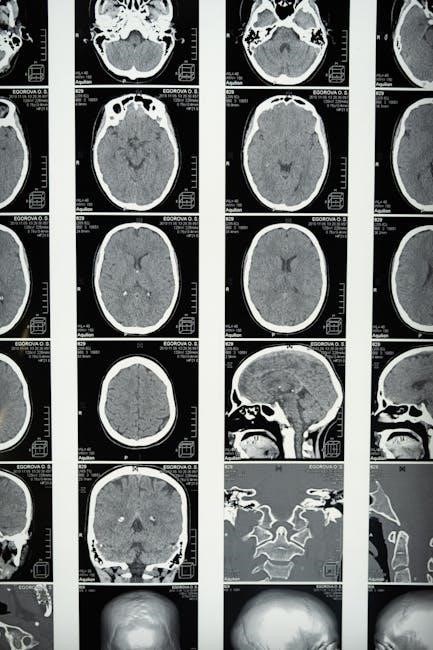

High-quality illustrations are paramount in any effective anatomy and physiology coloring workbook‚ especially when accessed as a PDF. The images should accurately represent anatomical structures‚ avoiding simplification to the point of inaccuracy. Look for workbooks that depict tissues‚ organs‚ and systems with realistic detail‚ showcasing their complex arrangements and relationships.

Illustrations should be free from ambiguity‚ clearly differentiating between various components. The level of detail should be appropriate for the intended audience – introductory workbooks may offer simpler depictions‚ while advanced resources will present more intricate anatomical features. When evaluating a PDF version‚ ensure the image resolution is sufficient to allow for clear coloring and identification of structures; blurry or pixelated images diminish the learning experience.

Furthermore‚ consider illustrations that demonstrate different views and sections of the anatomy‚ providing a comprehensive understanding of spatial relationships. Accurate depictions are crucial for building a solid foundation in anatomical knowledge;